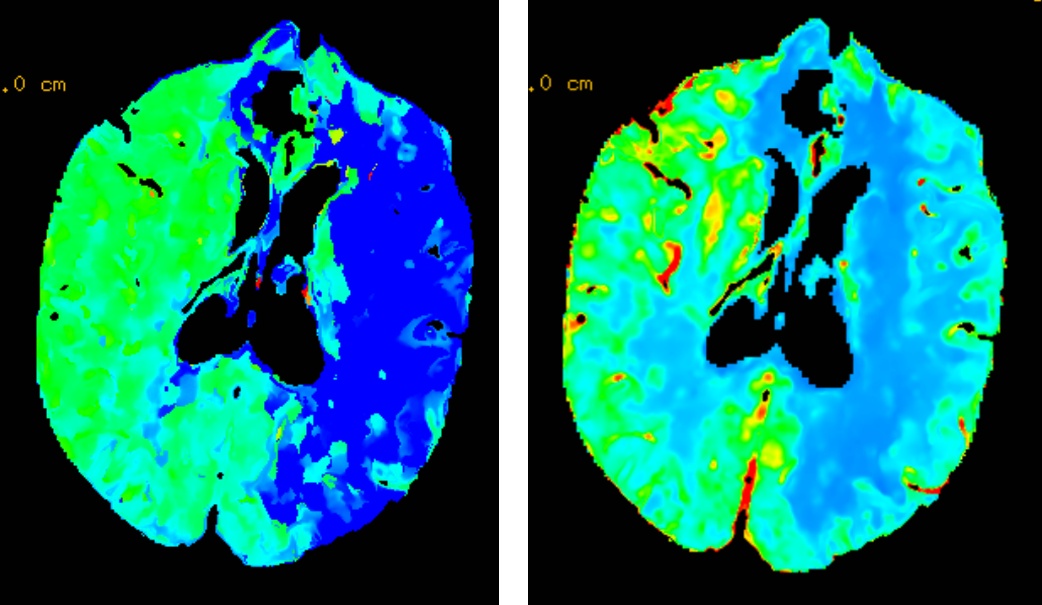

73岁男患,因“右侧肢体无力伴不能言语1小时余”入院;既往有脑梗死病史,未口服脑卒中二级预防药物治疗。入院时心电图提示心房颤动;急诊查颅脑CT排除颅内出血,且左侧大脑中动脉高密度征;急诊查头颈部CTA提示左侧大脑中动脉M1段闭塞,急诊查头颅CTP提示左侧大脑半球低灌注。考虑心源性脑栓塞,急诊行静脉溶栓桥接机械取栓治疗,最终病人恢复正常出院。

术前CTP提示左侧大脑半球低灌注